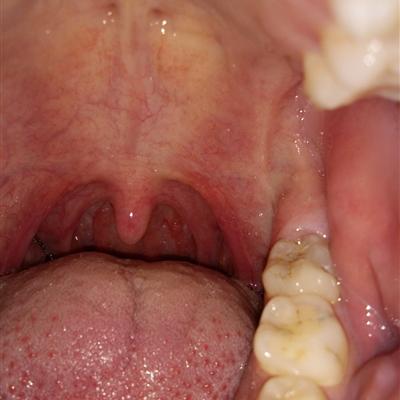

With the continuous improvement of people's living standards, personal health is also under serious threat. Thick and white tongue coating is a common phenomenon. When the tongue coating turns white, we feel as if the tongue has become thicker, some astringent feeling, sometimes accompanied by bitter mouth. What's the matter with tongue coating? Let me tell you about it.

First: the tongue coating is a layer of coating spread on the tongue. In fact, under normal circumstances, the tongue coating of ordinary people will turn white, but it is generally thin and white. If the tongue coating is thick and white, it means that the gastrointestinal tract in your body has changed.

Second, due to the strength of the stomach qi and the cold and heat of the body, different pathological tongue coating can be formed. Different symptoms of tongue coating reflect different gastrointestinal diseases.

Third: white moss can be seen in the normal disease-free people, but also in mild diseases, the onset of symptoms and signs, and the recovery period of the disease. Because the pathological changes inside the machine are not obvious, the change of tongue coating is close to the normal thin white tongue coating.